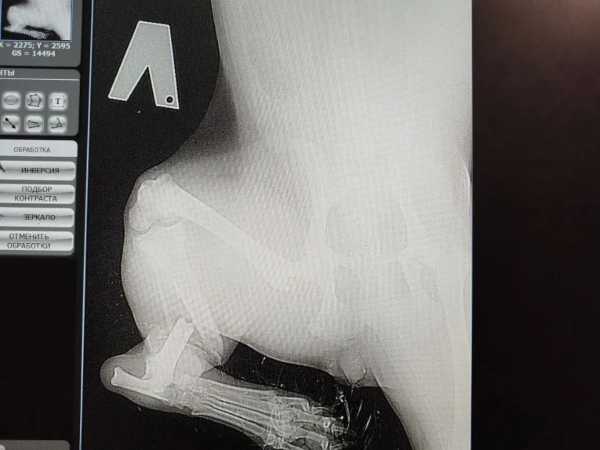

В ветеринарной клинике у малышки диагностировали сложный перелом задней лапы. Дополнительные обследования показали, что у щенка также обнаружен бабезиоз — опасное заболевание, которое переносят клещи. Кроме того, анализы выявили низкий уровень гемоглобина.

На данный момент щенок прооперирован и остается под наблюдением в клинике. Волонтеры настроены решительно и готовы продолжать борьбу за здоровье подопечной.